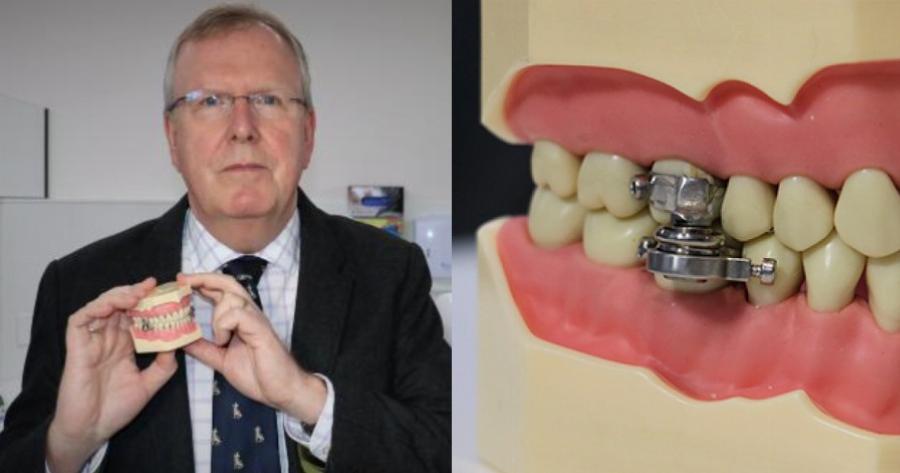

Μια συσκευή που κατασκευάστηκε στην Νέα Ζηλανδία

Αναπτύχθηκε από το Πανεπιστήμιο του Otago στη Νέα Ζηλανδία και επιστήμονες από το Leeds στο Ηνωμένο Βασίλειο για την αντιμετώπιση της παχυσαρκίας και μπορεί να τοποθετηθεί από οδοντίατρους και να χρησιμοποιεί μαγνητικά εξαρτήματα που επί της ουσίας “ασφαλίζουν” το στόμα.

Η συσκευή κατά της παχυσαρκίας “DentalSlim Diet Control”

Η συσκευή ονομάζεται DentalSlim Diet Control και επιτρέπει στους χρήστες της να ανοίγουν το στόμα τους σε πλάτος μόνο 2 χιλιοστών.

Ο καθηγητής Paul Brunton από το Πανεπιστήμιο του Otago είπε ότι το κύριο εμπόδιο, που σταμάτησε την απώλεια βάρους ήταν η «συμμόρφωση». Πρόσθεσε, ότι η συσκευή βοήθησε στο να δημιουργηθούν νέες συνήθειες».

Η ερευνητική ομάδα πίσω από το προϊόν περιελάμβανε τον Δρ Jonathan Bodansky του Leeds και τον Δρ Richard Hall του συμβούλου RMH στο Leeds.